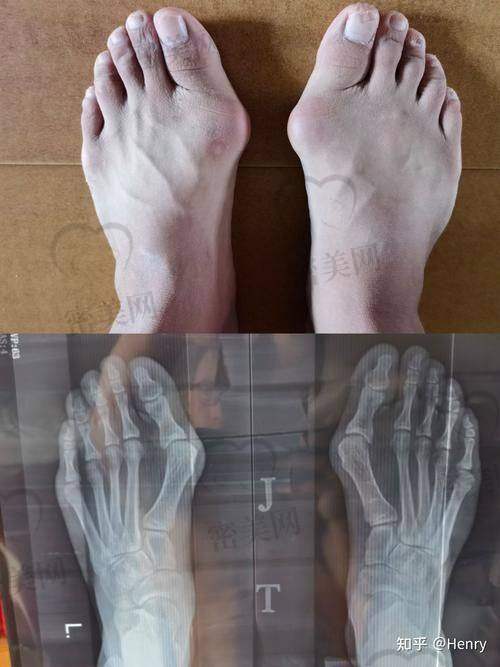

实例一:王女士,36岁

3年前在外地某骨科医院做了大脚骨矫正手术,术后不仅拇趾仍外翻,而且反复红肿疼痛,三年来不敢穿高跟鞋。

术前检查发现:拇趾角度依然28°,内侧突处骨赘未清理完全。苏敬达医生通过精细截骨矫正+细纹组织解剖修复足部正常应力线,并采用榫卯固定方式增加术后稳定性,术后一周伤口无红肿反应,45天后正常走路。

实例二:刘先生,41岁

重度大脚骨术后6个月仍感觉脚趾僵硬,走路像踩在石子上。术前拍片发现拇趾截骨段未愈合,固定状态松动。

苏医生术中严谨实施微接口刷新骨端疏松组织,使用取代钢钉的骨槽自锁结构固定,并通过足底肌腱柔性调整拉伸角度,术后3天即可轻负重,3个月修复健步如飞。